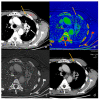

Dual-energy computed tomography (DECT) is one of the most promising technological innovations made in the field of imaging in recent years. Thanks to its ability to provide quantitative and reproducible data, and to improve radiologists' confidence, especially in the less experienced, its applications are increasing in number and variety. In thoracic diseases, DECT is able to provide well-known benefits, although many recent articles have sought to investigate new perspectives. This narrative review aims to provide the reader with an overview of the applications and advantages of DECT in thoracic diseases, focusing on the most recent innovations. The research process was conducted on the databases of Pubmed and Cochrane. The article is organized according to the anatomical district: the review will focus on pleural, lung parenchymal, breast, mediastinal, lymph nodes, vascular and skeletal applications of DECT. In conclusion, considering the new potential applications and the evidence reported in the latest papers, DECT is progressively entering the daily practice of radiologists, and by reading this simple narrative review, every radiologist will know the state of the art of DECT in thoracic diseases.